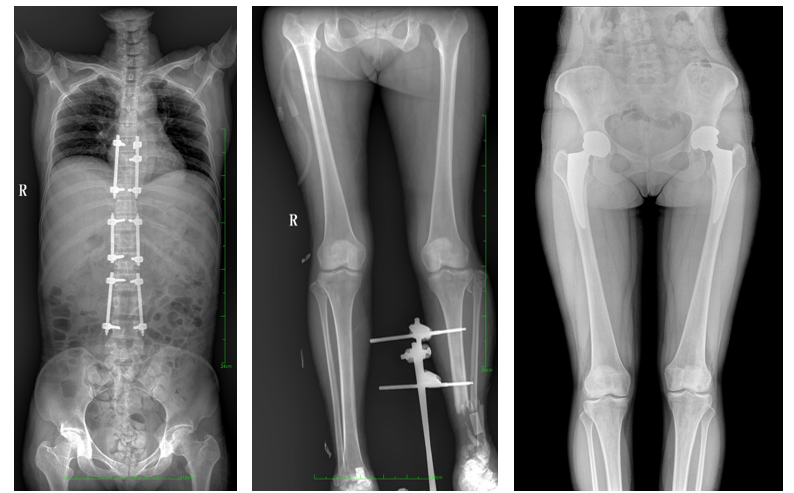

DR常用于人體胸部及骨骼攝片,也可拍攝其他部位,例如腹部、牙齒、頭顱等。使用人群較廣,可以進(jìn)行全身各部位檢查,曝光后幾秒就可獲得數(shù)字影像,成像速度快,且價(jià)格便宜,極大提高了工作效率,方便臨床重癥、急癥患者的診治。

站立位X線(xiàn)影像是測(cè)定人體負(fù)重骨骼的生物學(xué)力線(xiàn)、對(duì)稱(chēng)結(jié)構(gòu)平滑線(xiàn)及脊柱側(cè)凸角等首選的檢查內(nèi)容,這和CT、MRI臥位成像,在臨床意義上有著根本區(qū)別。在脊柱及下肢的臨床治療過(guò)程中,一般需要進(jìn)行矯正和關(guān)節(jié)置換手術(shù)治療,在對(duì)其進(jìn)行手術(shù)前后,均需要拍攝站立位負(fù)重X光片以便分析病情,明確診斷和觀察治療效果。

常規(guī)DR拍攝面積有限,最大規(guī)格僅有43cm,但成人男性全脊柱長(zhǎng)度平均為70-75cm,女性為66-70cm,而雙下肢更長(zhǎng)。普愛(ài)醫(yī)療PLX8600動(dòng)態(tài)DR的43cm*86cm超大有效視野,可一次成像全脊柱及雙下肢。